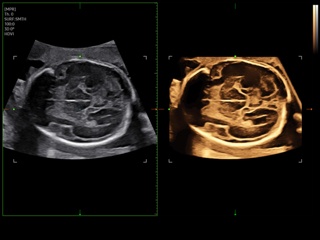

Atlas of ultrasound images - obsterics

In the section "Оbsterics" of atlas the results of ultrasonic examinations of pregnant women with different durations of gestation are represented. Here you can see images of internally organs, cerebrum, cordis and the sex of the fetus, the sonograms of multiple pregnancy, the blood flow in placenta and umbilical cord, defects of fetal`s development, etc.